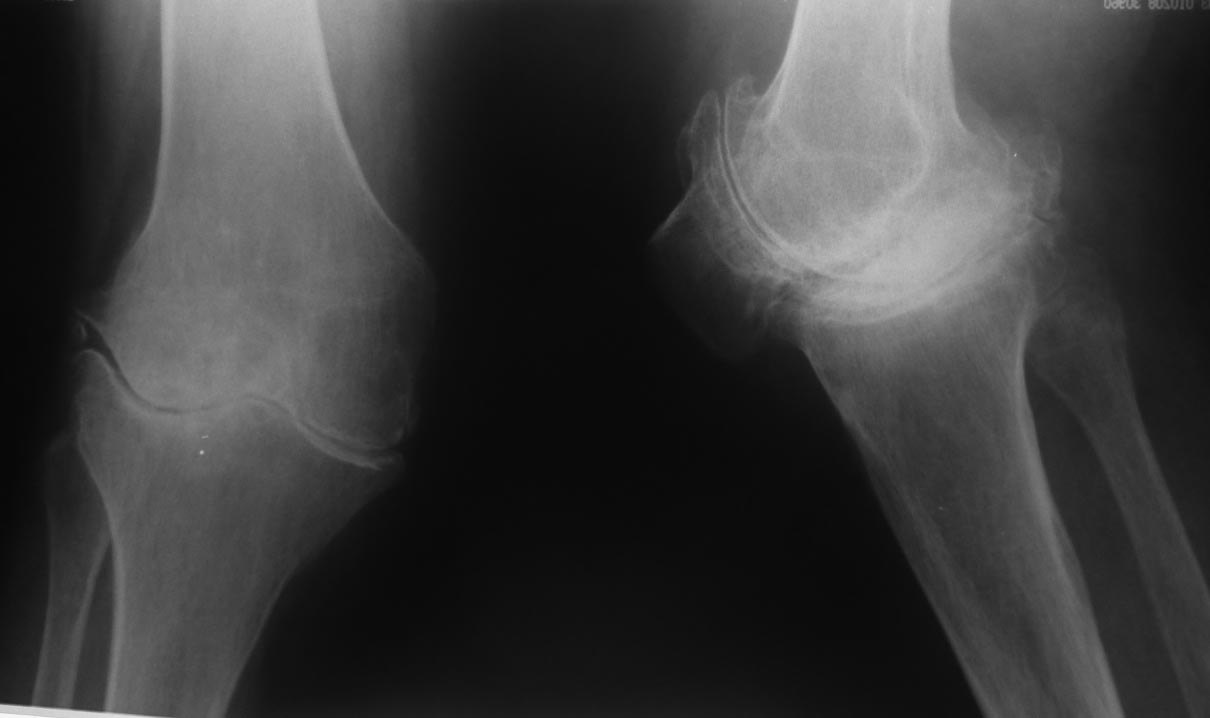

袙芯褌 芯斜械褖邪薪薪褘泄 胁 褔械屑-褌芯 锌芯褏芯卸懈泄 褋谢褍褔邪泄. 袩邪褑懈械薪褌泻邪 58 谢械褌 褋 褌褟卸械谢褘屑

褉械胁屑邪褌芯懈写薪褘屑 邪褉褌褉懈褌芯屑. 袨锌械褉懈褉芯胁邪谢 胁 2013 谐. 袙 芯写薪褍 褋械褋褋懈褞 褋写械谢邪谢

褔褉械褋泻芯卸薪芯 锌芯胁褌芯褉薪褍褞 芯锌械褉邪褑懈褞 薪邪 褋褌芯锌械 (褉邪薪褜褕械 谐写械-褌芯 芯锌械褉懈褉芯胁邪谢懈,

锌邪褑懈械薪褌泻邪 锌褉懈械褏邪谢邪 懈蟹写邪谢械泻邪) 懈 屑邪谢芯懈薪胁邪蟹懈胁薪褘泄 邪褉褌褉芯写械蟹 谐芯谢械薪芯褋褌芯锌薪芯谐芯

褋褍褋褌邪胁邪 (懈屑械谢邪褋褜 胁邪褉褍褋薪邪褟 写械褎芯褉屑邪褑懈褟, 泻邪泻 泻芯屑锌械薪褋邪褑懈褟 胁邪谢褜谐褍褋邪 泻芯谢械薪邪,

薪邪 褎芯薪械 胁褘褉邪卸械薪薪芯泄 褉械胁屑邪褌芯懈写薪芯泄 邪褉褌褉芯锌邪褌懈懈). 袗 褔械褉械蟹 薪械写械谢褞鈥

锌褉芯褌械蟹懈褉芯胁邪薪懈械 泻芯谢械薪薪芯谐芯 褋褍褋褌邪胁邪 (褎懈斜褉芯蟹薪褘泄 邪薪泻懈谢芯蟹 锌芯褋谢械 泻芯谐写邪-褌芯

胁褘锌芯谢薪械薪薪芯泄 褋懈薪芯胁褝泻褌芯屑懈懈, 谐褉褍斜邪褟 胁邪谢褜谐褍褋薪邪褟 写械褎芯褉屑邪褑懈褟). 袩芯薪褟褌薪芯, 褔褌芯

芯锌芯褉芯褋锌芯褋芯斜薪芯泄. 袨褋薪芯胁薪芯械 锌芯卸械谢邪薪懈械 锌芯 泻芯谢械薪泻械 斜褘谢芯, 褔褌芯斜褘 褋谐懈斜邪谢邪褋褜 褏芯褌褜

薪械屑薪芯谐芯 写谢褟 锌芯褏芯写芯胁 胁 褌械邪褌褉. 袙 泻芯薪械褔薪芯屑 褋褔械褌械, 褋褍褋褌邪胁 褋谐懈斜邪谢褋褟 写芯 90 谐褉.